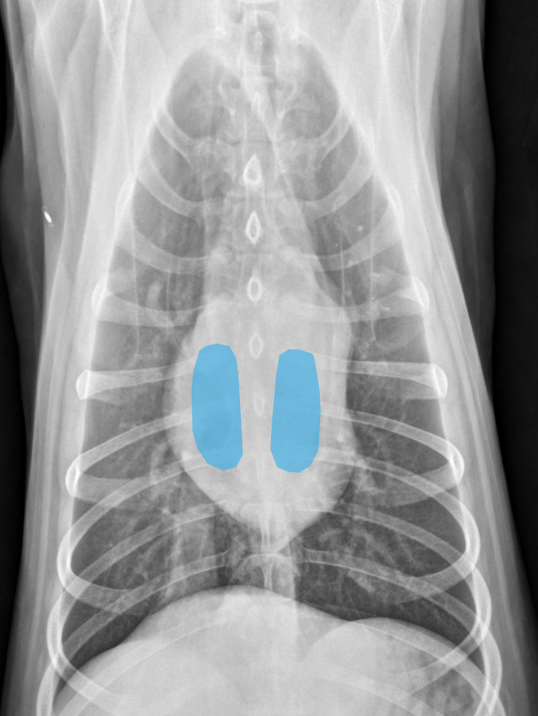

Lung Pattern? Where is the hilus?

Normal lungs